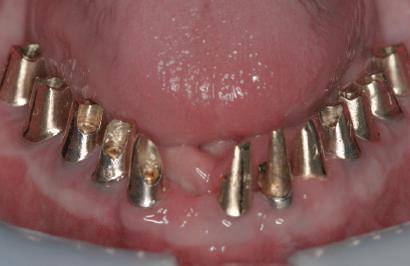

Cazul (4)

Bonturi provizorii

Acest pacient s-a prezentat cu dentiţia mandibulară laterală dreaptă eşuată din cauza unei fracturi radiculare verticale şi a cariei secundare. Autorii au utilizat cilindri de bonturi provizorii, cu şurub, ca metodă iniţială de retenţie pentru puntea provizorie după prima etapă de tratament, care a inclus extracţii şi inserarea de implanturi. Atitudine: Cilindrii temporari înşurubaţi pe implanturi după inserare sunt prezentaţi în fig 13. Ei au fost cimentaţi la carcasa acrilică prefabricată construită pe baza wax-up-ului diagnostic al pacientului (fig. 14). După îndepărtarea acrilatului excesiv, s-a

inserat proteza provizorie fixată cu şurub (fig. 15).

Cazul (5)

Bonturi conice utilizate ca bonturi temporare

Pacienta prezenta boală parodontală generalizată, cu leziuni endodontice secundare. A refuzat ferm proteze mobilizabile provizorii. Extracţiile totale mandibulare şi maxilare s-au realizat în prima fază a tratamentului. În această fază iniţială nu s-ar putea insera toate implanturile din cauza necesităţii de vindecare a anumitor

Cazul (4): Bonturi provizorii

Figurile

13. Cilindrii temporari înşurubaţi pe implanturi.

14. Cilindrii cimentaţi la o carcasă prefabricată din acrilat.

15. Proteza fixă provizorie fixată cu şuruburi.

locaţii grefate. Implanturile plasate în această primă fază au fost încărcate cu bonturi conice şi, în unele cazuri, cu omologii lor angulaţi (fig. 16, 17).

S-au selectat bonturi standard de titan pentru a evita schimbarea sau refrezarea bonturilor individualizate mai scumpe; în plus nu necesită utilizarea cimentului temporar în proximitatea sau în jurul locaţiilor chirurgicale, întrucât utilizează doar şuruburi pentru retenţie.

Atitudine: Până la dobândirea vindecării totale a ţesuturilor şi a implanturilor secundare s-au utilizat bonturi standard de titan. Fig. 18 prezintă bonturile individualizate maxilare şi mandibulare aplicate iar fig. 19 un prim-plan al cadranelor de partea dreaptă a pacientului, afişând finalizarea cazului la 15 luni după începerea tratamentului iniţial. Recesiile se pot obiectiva corespunzător 1.4. şi 1.3. În acest caz, s-a încercat minimizarea susceptibilităţii la recesie prin implicarea bonturilor temporare standard fixate cu şurub în cursul fazelor de vindecare pe toată durata etapelor iniţiale ale tratamentului.

În pofida acestor eforturi, totuşi, recesia a apărut în anumite regiuni unde implanturile erau plasate vestibular. Ulterior, s-a încercat grefarea ţesutui moale din jurul locaţiilor cu recesie, dar fără succes.